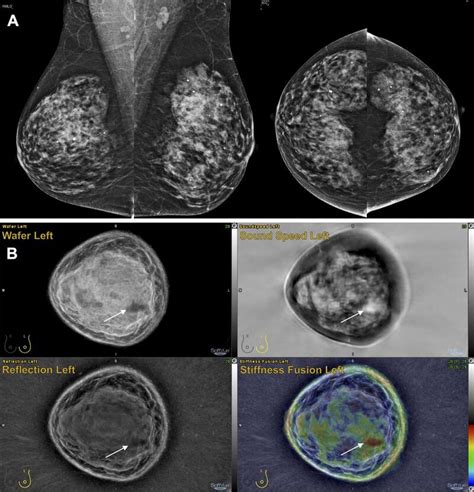

TitleUS Tomo for Dense Breasts - The Imaging Wire

Dimensions2075 × 2155 px